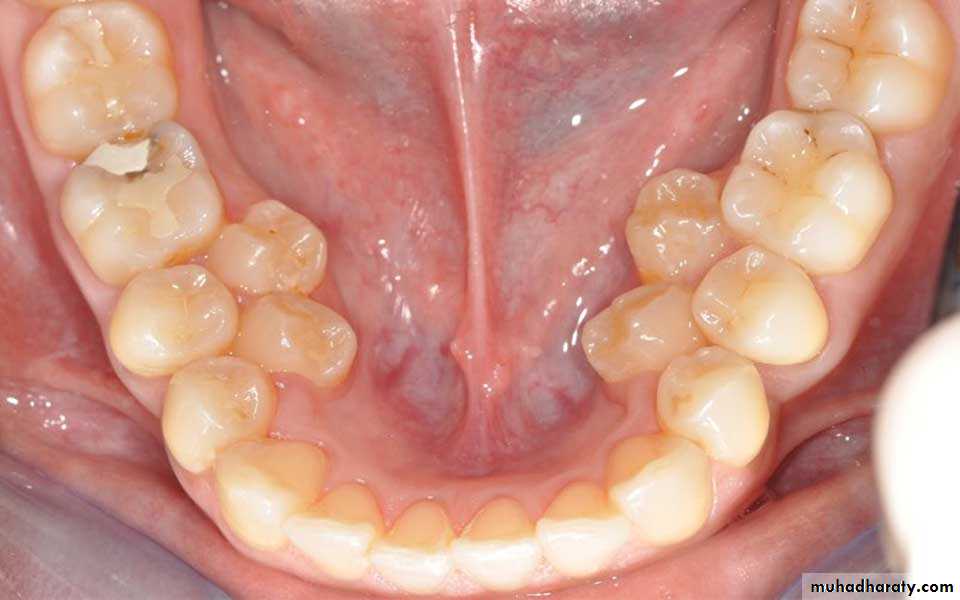

4- Premature loss of deciduous teeth

The early loss of primary teeth should be considered as a “Malocclusion Maker”Deciduous teeth not only serve as organs of mastication, but as spacesavers for permanent teeth. Loss of a deciduous 2nd molar will lead to mesial driftof the 1st permanent molar and blocking of

erupting 2nd premolars.In this cases appropriate

space maintainers should be given.